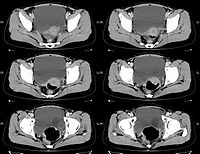

影像学检查可明确诊断。B型超声检查可显示膀胱内有薄壁囊性肿块。静脉尿路造影典型者表现为输尿管末端“蛇头”状膨大,伴或不伴肾输尿管扩张积水,合并重复畸形时亦可显示。膀胱镜检可见输尿管开口处呈囊状扩张,开口呈针尖样随输尿管蠕动时张时缩。